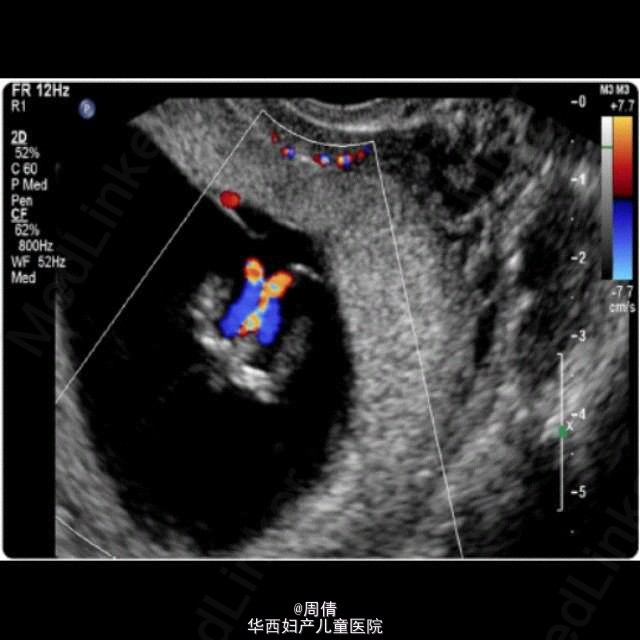

超声诊断单绒毛膜双胎羊膜囊融合一例

37岁女性,G3P1,自然受孕9w。 阴道超声示:子宫腔单个妊娠囊内2个胎儿,单绒毛膜。拥有共同的卵黄囊,在脐周相互连接。